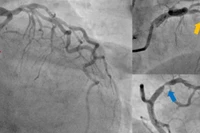

Nhận định khả năng bị huyết khối tĩnh mạch não, các bác sĩ chỉ định chụp MRI tĩnh mạch não có thuốc cản quang. Kết quả phát hiện huyết khối bán phần tĩnh mạch cảnh trong và xoang tĩnh mạch ngang bên phải. Nếu chậm trễ, người bệnh có thể đối mặt nguy cơ liệt vĩnh viễn hoặc tử vong.

Phát hiện kịp thời huyết khối tĩnh mạch não giúp người bệnh hồi phục nhanh/Ảnh VTV